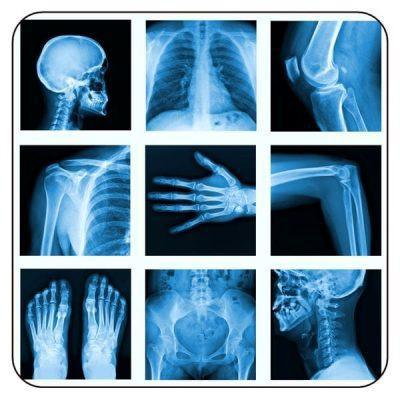

Most NPs have a basic understanding of x-ray interpretation, but many question the “why and how” of radiology, especially with more complicated patient films. This two-part session takes the participant from a basic understanding of the shades of black and white on an x-ray film to the ability to identify pneumonia, CHF, cardiomegaly, bowel obstruction, spine injuries, Salter Harris fractures, and much more. Within 2 ½ hours, it’s from novice to expert with radiology.